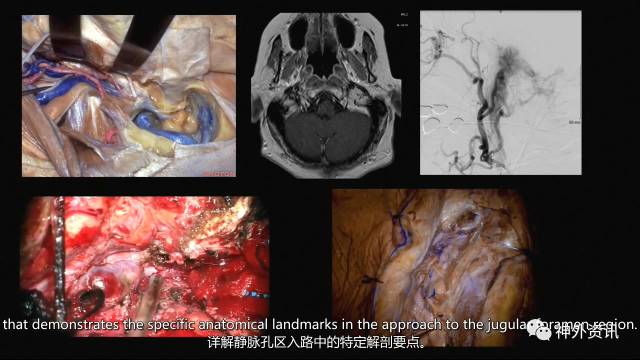

今天为大家分享的是The Rhoton Collection系列解剖视频《The Postauricular Transtemporal Approach to the Jugular Foramen》耳后经颞入路至颈静脉孔区。

尸头解剖视频详解

实际手术视频详解